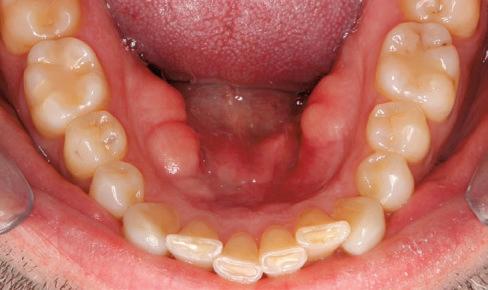

(Full orthodontic treatment cost: $4,200)

For information, visit www dentistry

UBC Dentistry is screening patients

of age and

who require Braces

ubc.ca/gradortho Graduate Orthodontics Program To arrange a screening appointment: Call between 8:30 am – 4 pm (Monday to Friday) 604-827-4991 or email gradorthoclinic@dentistry.ubc.ca T H E U N I V E R S T Y O R B R I T S H C O L U M B A UBC Dentistry is screening patients 7yearsofageandolderwhorequire Braces (Full orthodontic treatment cost: $1,000to$4,200) For information, visit wwwdentistryubcca/gradortho GraduaeOrhodon csProgram Toarrangeascreeningappointment: 604-827-4991(12years&older) 604-827-0706(7to10yearsold) oremailgradorthoclinic@dentistryubcca HEALTHY CHOICES MADE SIMPLE NUTRITION TOURS ARE BACK! Sign up for a FREE nutrition tour personalized to your needs with the Choices Nutrition Team in-store or online at choicesmarkets.com PLANT-BASED GLUTEN-FREE ANTI-INFLAMMATORY GUT-FRIENDLY 100% BC OWNED AND OPERATED VANCOUVER | NORTH VANCOUVER BURNABY SOUTH SURREY ABBOTSFORD KELOWNA COMING SOON TO PARKSVILLE! THANK YOU FOR RECYCLING THIS NEWSPAPER.